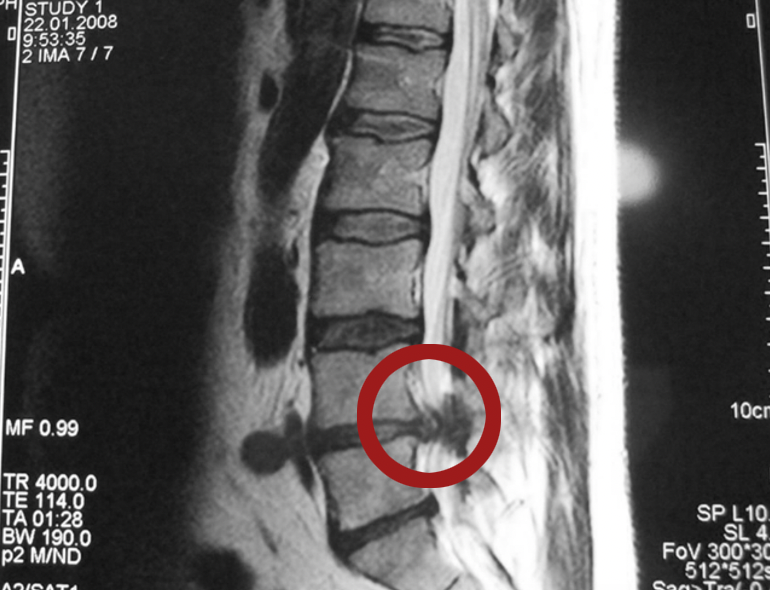

Межпозвоночная

грыжа -